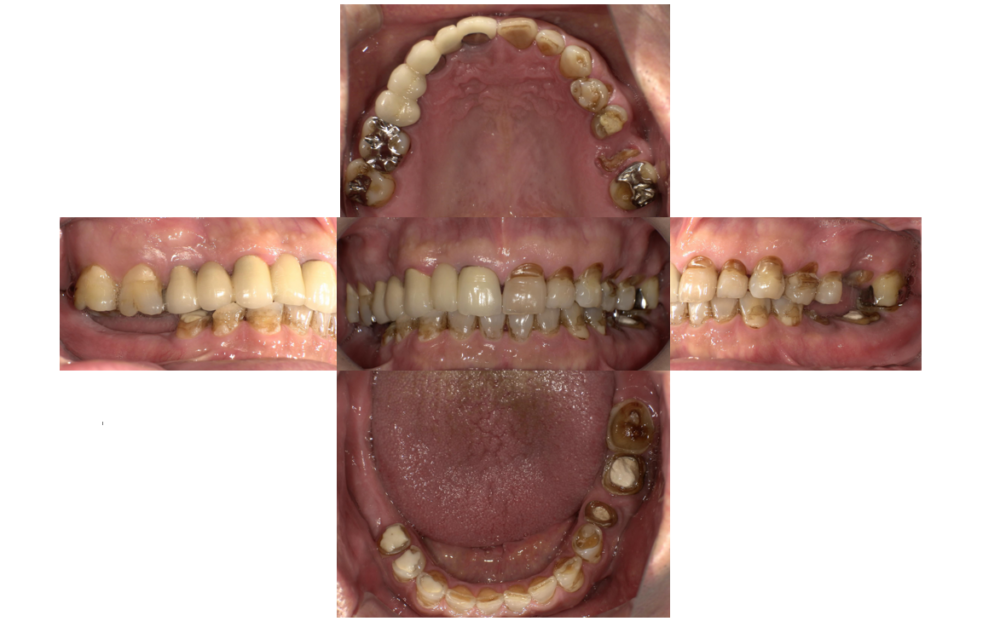

症例3

治療前

治療後

| 主訴 | 歯を入れたい |

|---|---|

| 診断 |

「右下」67欠損 |

| 治療内容 | 右下67左下6インプラント、左上⑤6⑦ジルコニアブリッジ |

| 年齢・性別 |

68歳 男性 |

| 治療期間 |

8ヶ月 |

| 治療費用 | ①左上⑤6⑦ジルコニアブリッジ¥264000 ②右下67左下6インプラント(3本) 診査診断¥22000+一次手術(京セラ)¥825000+左下6GBR¥110000+上部構造¥429000 総額¥1386000 |

| リスク・副作用 | インプラント周囲炎、インプラント上部構造の緩み |